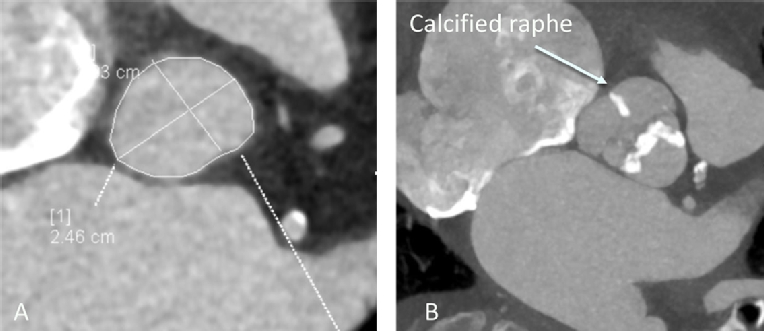

Patient evaluation can be advanced before the role of radiation is recognised. Echocardiographic features are very typical: in particular, heavy thickening of the aortic/mitral continuity and anterior mitral leaflet should alert the assessor to the possibility of radiotherapy (Figure 2).

Figure 2. A) Parasternal long-axis view demonstrating the typical features of radiation-induced heart valve disease. B) 3D volume rendering demonstrating severe circumferential aortic calcification. C) & D) Extensive valve and proximal coronary artery calcification and valvular calcification.

Assessment of radiation-induced heart disease

Evaluation of patients is more detailed than in those with conventional aortic valve disease. A multimodality approach is always required. Assessment of the severity of the aortic valve stenosis is best undertaken using echocardiography. The standard measures of severity apply. However, it is common for patients to express either low flow, or paradoxical low flow pattern (with a transaortic flow rate of less than 35 mls/m2) because of radiotherapy-induced myocardial dysfunction. When the ejection fraction is preserved, significant LV dysfunction can still be demonstrated by careful attention to longitudinal function, in particular global longitudinal strain (27).

Gated CT evaluation of the chest is mandatory. This offers an opportunity to confirm the severity of the aortic valve stenosis, although using the aortic valve Agatston score is not validated in this context. The proximal coronary arteries can be examined, although the high level of calcification at and around the aortic root may make accurate assessment of the coronary difficult, signalling the need for invasive angiography. The CT assessment should include the thoracic aorta to describe the extent and location of aortic calcification and how this may affect surgical access. Finally, using the appropriate lung windows an assessment of the location and extent of pulmonary fibrosis should be undertaken.